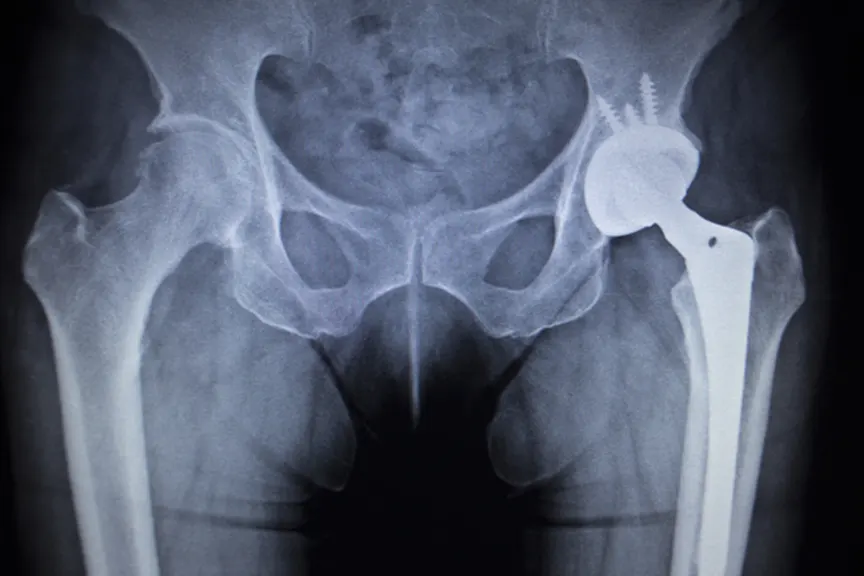

髋关节置换术

人们经常对臀部的组织和骨骼造成严重的退行性损伤。最近的几项研究侧重于髋关节替代品的成果。古德曼和同事然而,与术后两年的人和人民的髋关节替代品相比,髋关节替代品。虽然随着患者在手术时患者比OA的患者在手术患者中越来越差,但手术后两年内没有痛苦或功能差异。